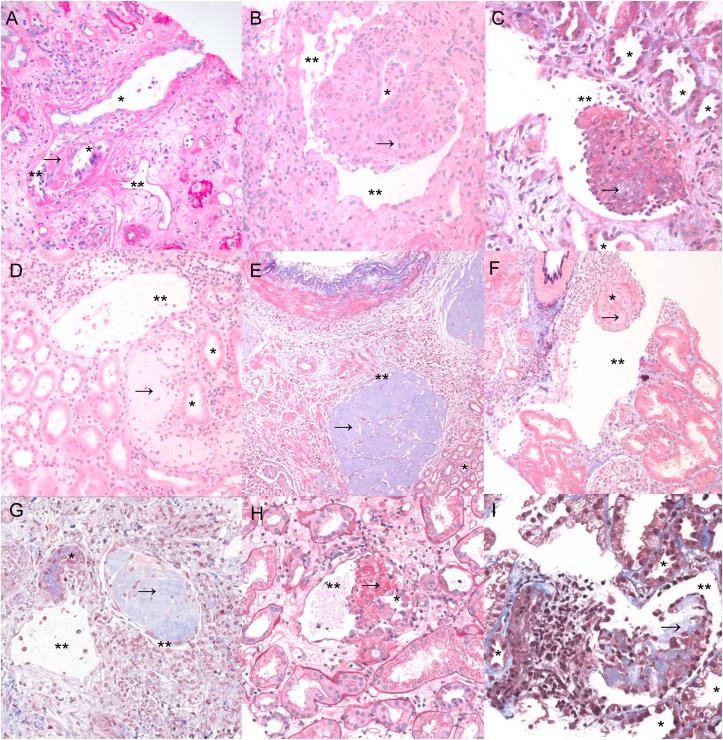

RATIONALE & OBJECTIVE: Pathological connection between the kidney tubules and veins is known as a microscopic tubulovenous communication we refer to as a tubulovenous fistula (TVF). This finding has been reported in a few small case reports, but no systematic examination of cases across various clinical settings detailing their histologic spectrum and associated clinical/pathologic findings has been performed.

In total, 72.7% of TVF cases were from native kidney biopsies. Median patient age was 66 (range, 25-84) with a male predominance (68.2%). Clinically, 82.4% had microscopic hematuria, and 17.6% had gross hematuria. TVFs were usually singular and involved arcuate size veins. Microscopically, 95.5% of cases had acute tubular injury, and 73.3% had at least focal pathologic intratubular casts/calcium crystals. In total, 56.3% of native cases had interstitial nephritis. Of the transplant cases (n = 6), 66.7% exhibited rejection.

This is the largest case series exploring the clinical and histologic features associated with TVFs in the kidney. Our findings support the assertion that TVFs are associated with hematuria without glomerulonephritis and occur in the setting of significant tubular injury, intratubular casts/crystals, and obstructive phenomena likely because of disruption of tubular basement membranes adjacent to veins.